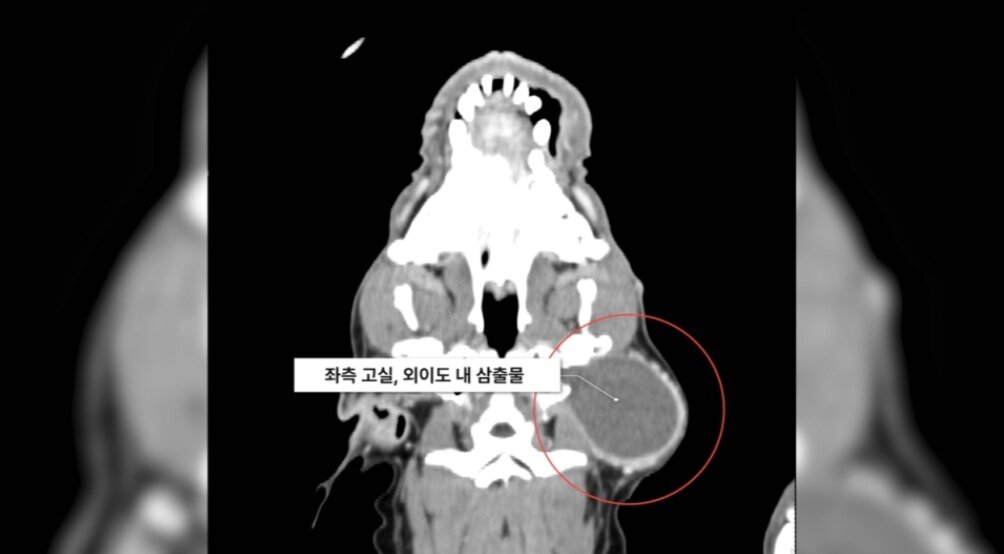

본문 이미지 - 민트는 CT 검사 결과 염증이 중이를 넘어 뇌로 확산되기 직전이었다(SD동물의료센터 제공). ⓒ 뉴스1

민트는 CT 검사 결과 염증이 중이를 넘어 뇌로 확산되기 직전이었다(SD동물의료센터 제공). ⓒ 뉴스1